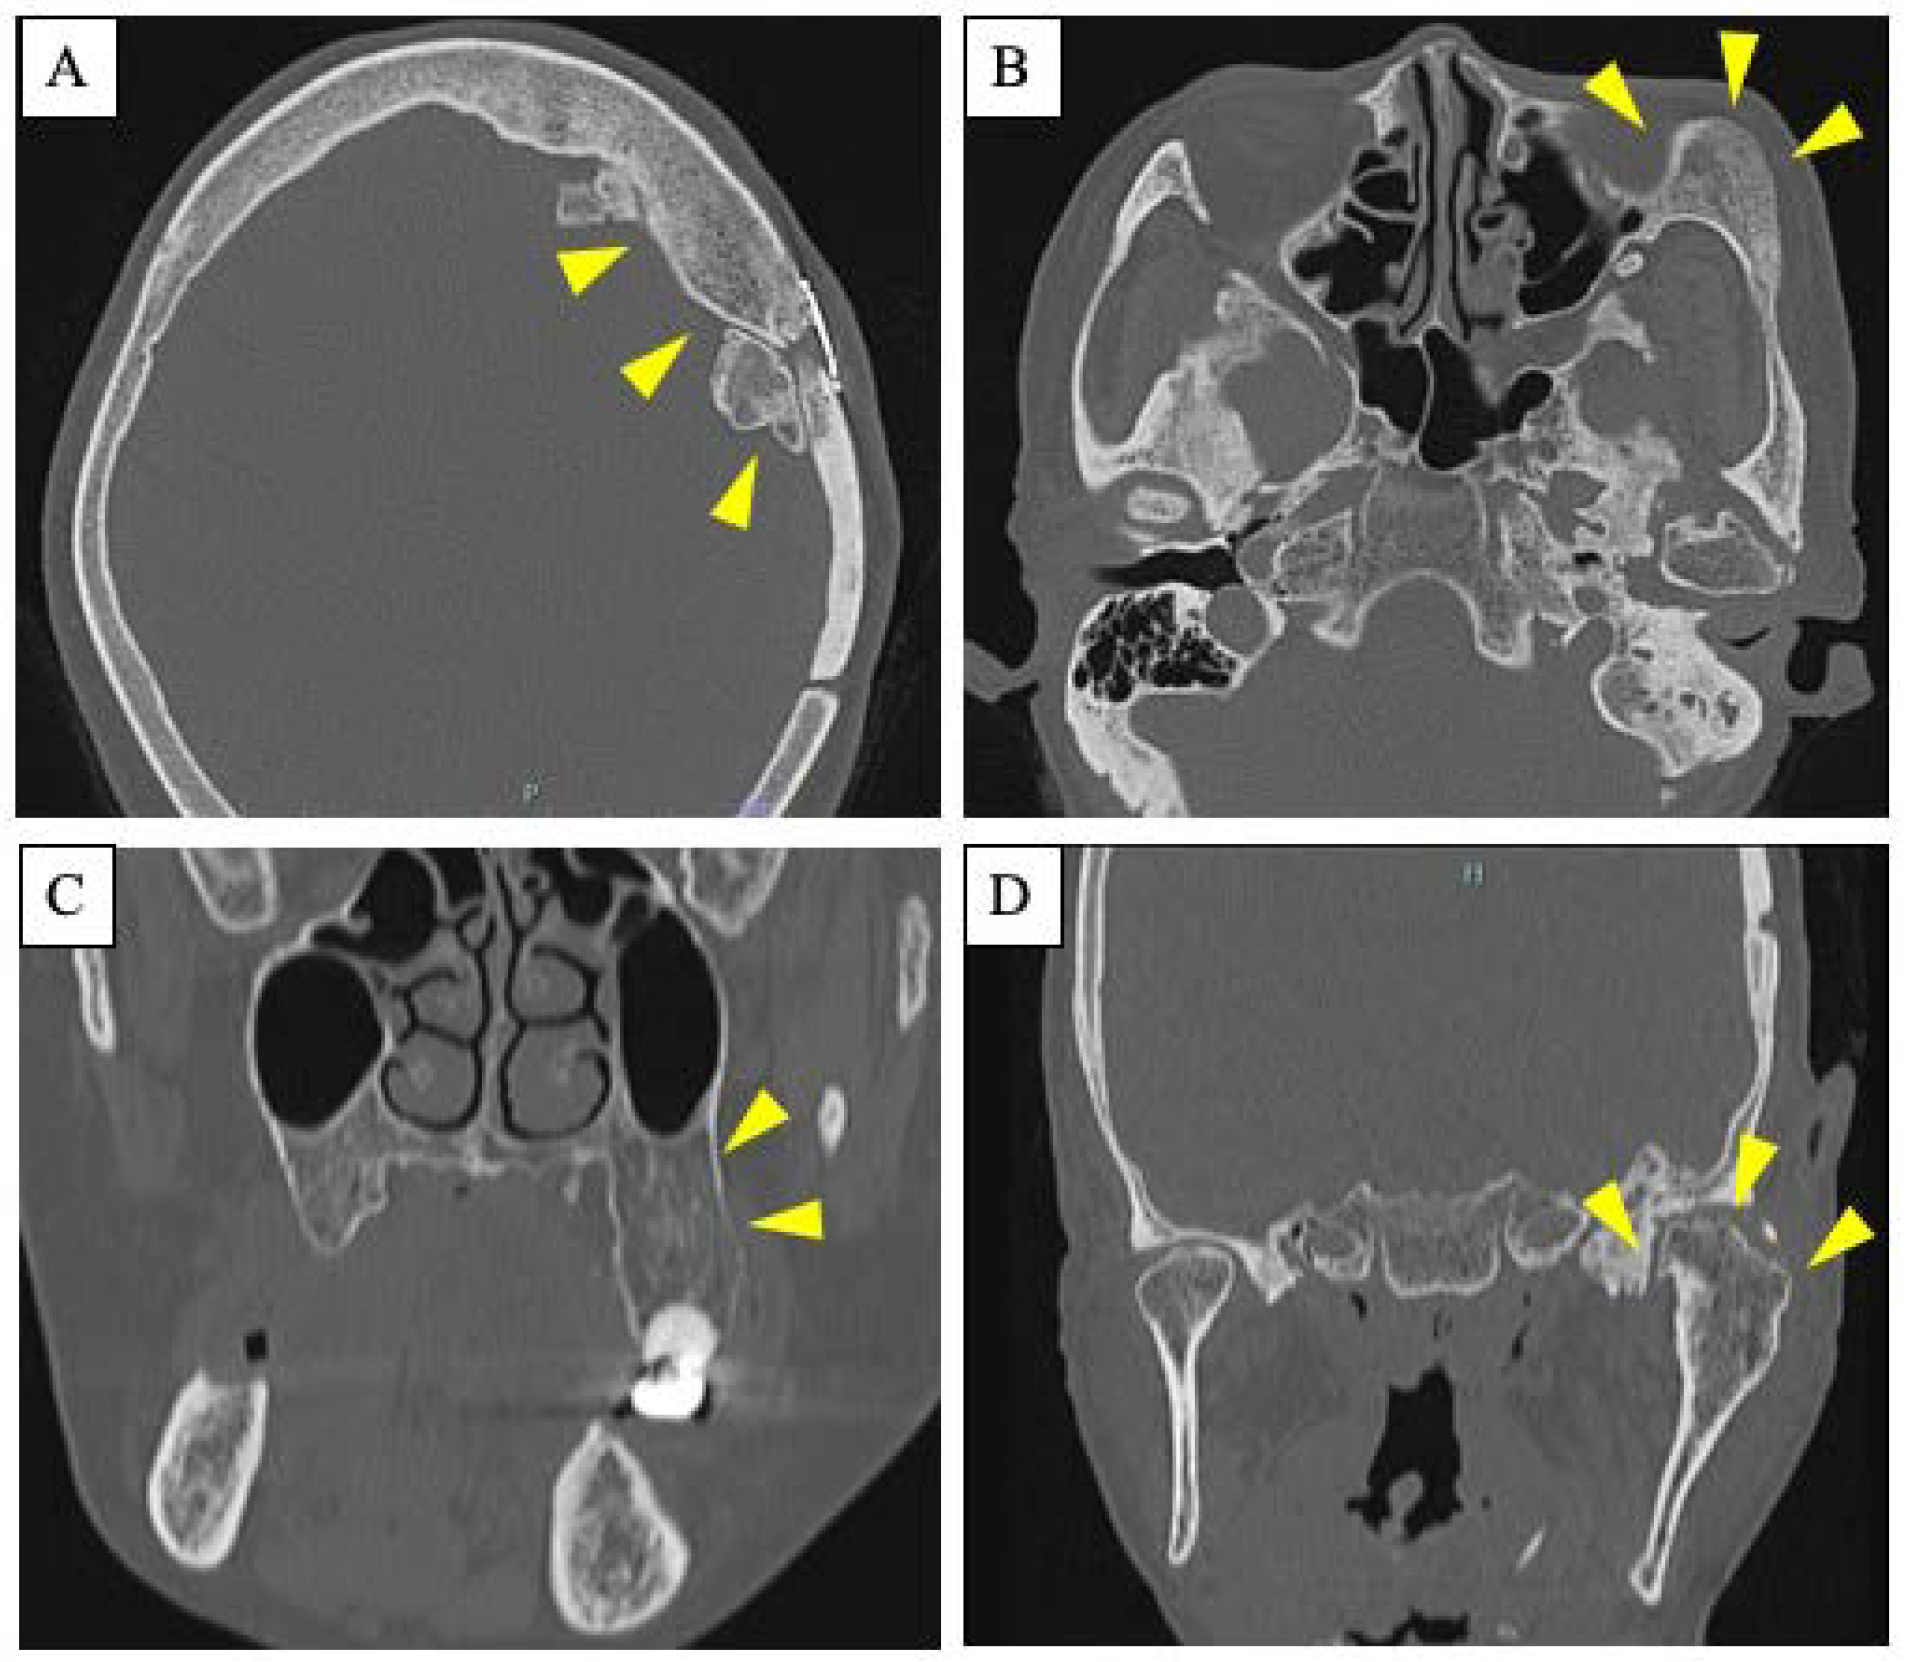

2. Case Presentation